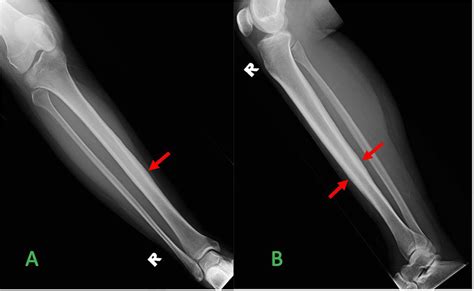

Alright, let’s get to the main event: the pseudoarthrosis tibia X-ray. This is the go-to imaging tool for docs trying to figure out if you’ve got this non-union thing going on. When they suspect pseudoarthrosis, the standard X-ray is usually the first step, and often, it’s enough to give them a pretty good idea. What are they actually looking for on these films, you ask? They’re hunting for signs that the bone hasn’t knitted back together . A healthy fracture healing will show progressive callus formation – that’s new bone trying to bridge the gap. In pseudoarthrosis, you’ll often see a clear gap between the broken bone ends, and instead of solid bone bridging it, there might be fibrous tissue or even cystic changes in the bone ends. Sometimes, the bone ends can become rounded off and sclerotic (that means hardened and denser) because they’re not being used properly, and the body’s trying to adapt to the instability. Another key indicator is motion at the fracture site . While you can’t directly see motion on a static X-ray, the consequences of that motion are visible. You might see widening of the fracture line over time, or displacement of the bone fragments that wouldn’t happen if the bone were solidly healed. They’ll also look at any hardware – like screws, plates, or rods – that might have been put in during initial surgery. Is the hardware intact? Is it loose? Is there any sign of infection around it (like bone resorption or bone spurs)? The X-ray is basically a detective’s magnifying glass, revealing clues about the past injury and the body’s current, failed attempt at repair. It’s essential to compare current X-rays with previous ones if available, as this allows the radiologist and orthopedic surgeon to track the progression (or lack thereof) of healing over time. This comparison is vital in confirming a diagnosis of pseudoarthrosis, as a single X-ray might not always be definitive, especially in the early stages of non-union.

Radiologists are like the skilled detectives of the medical world when it comes to interpreting X-rays. For a pseudoarthrosis tibia X-ray , they’re scrutinizing the image with a fine-tooth comb. The primary goal is to identify lack of bony union . This means they’re looking for a distinct gap between the fractured bone ends. In a successfully healing fracture, this gap would be filled with callus, a new bone formation that gradually ossifies. In pseudoarthrosis, this callus is either absent, inadequate, or has failed to mature into solid bone. They will specifically look for atrophic changes , which means the bone ends are thin, pointed, or have lost their normal shape due to disuse and lack of stability. Conversely, they might see hypertrophic changes , where the bone attempts to heal by forming excessive, often disorganized, bone spurs (callus) around the ends, but these spurs don’t actually bridge the gap. This is often called